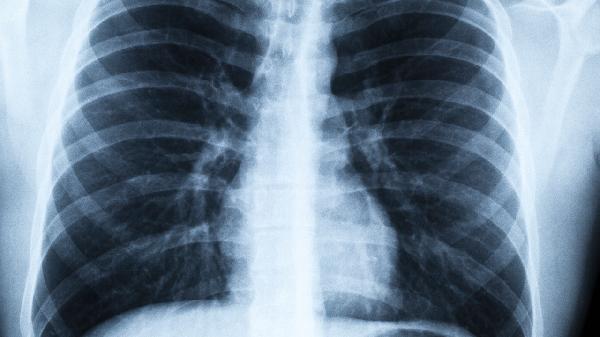

1、低剂量螺旋CT

比胸片敏感度高6倍,能发现2毫米的微小结节。45岁以上吸烟者应每年检查1次,辐射量仅相当于乘坐2小时。